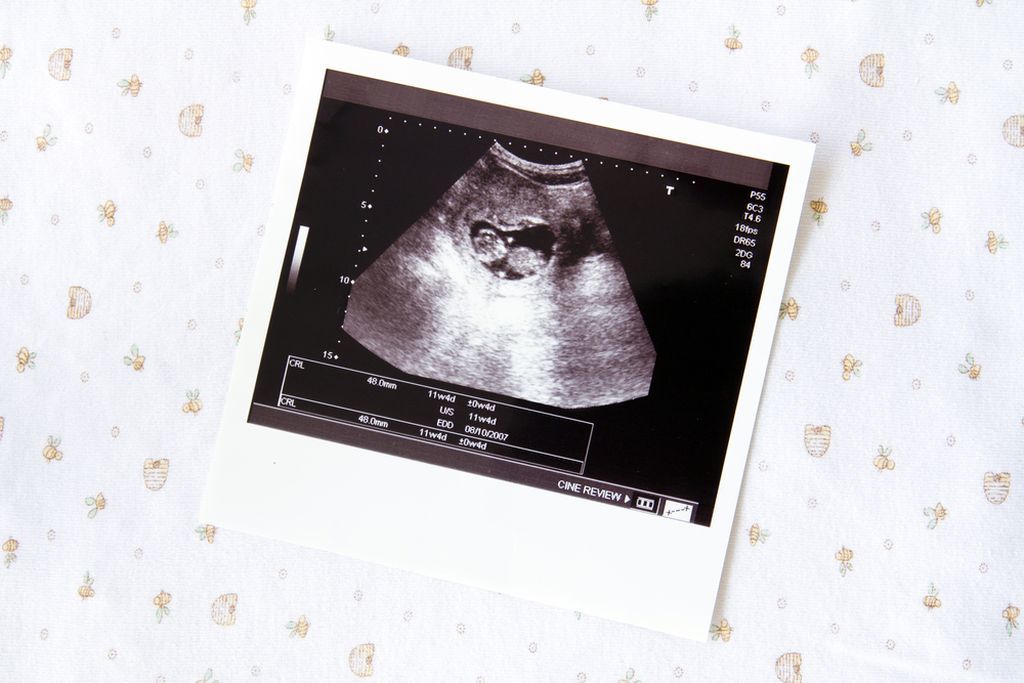

Η πρώτη φορά που «βλέπετε» το μωρό σας είναι ανάμεσα σε ασπρόμαυρες σκιές. Όμως, το υπερηχογράφημα δεν σας χαρίζει μόνο την πρώτη φωτογραφία του. Βοηθάει το γιατρό να βεβαιώνεται ότι όλα πάνε καλά.

Πρόκειται για μια εξέταση που πραγματοποιείται με ειδικό μηχάνημα (υπερηχοτομογράφος), το οποίο χρησιμοποιώντας τα ηχητικά κύματα αναπαράγει εικόνες του εμβρύου και των εσωτερικών οργάνων του, του πλακούντα και του αμνιακού σάκου. Έτσι, ο γιατρός μπορεί να βεβαιωθεί ότι το μωρό αναπτύσσεται σωστά και να κάνει μετρήσεις ώστε να υπολογίσει το ύψος και το βάρος του. Η διαδικασία με την οποία πραγματοποιείται η εξέταση είναι απλή και εντελώς ανώδυνη: Ο γιατρός, αφού απλώσει στην κοιλιά σας ένα τζελ, ώστε να εφάπτεται σωστά η κεφαλή του μηχανήματος (ηχοβολέας) με το δέρμα, κινεί τον ηχοβολέα ελέγχοντας στην οθόνη και αποθηκεύοντας τις εικόνες. Κατά μέσο όρο, μία εξέταση με υπέρηχο διαρκεί περίπου 15-20 λεπτά.

- Το δεύτερο γίνεται μεταξύ 11ης και 14ης εβδομάδας και απεικονίζει τη θέση του πλακούντα, την ανάπτυξη των οργάνων του εμβρύου, ενώ ανιχνεύονται τυχόν ανωμαλίες. Επιπλέον, γίνεται μια ειδική μέτρηση που ονομάζεται «αυχενική διαφάνεια» και υπολογίζει την πυκνότητα της περιοχής του πίσω μέρους του λαιμού του μωρού. Ο υπέρηχος αυτός συνδυάζεται με εξέταση αίματος, που εκτιμά την πιθανότητα ύπαρξης γενετικών ανωμαλιών, όπως το Σύνδρομο Down (PAPP-A test). Κατά τη διενέργεια της αυχενικής διαφάνειας, μπορούμε να δούμε το φύλο του εμβρύου (με πιθανότητες περίπουν 75%).